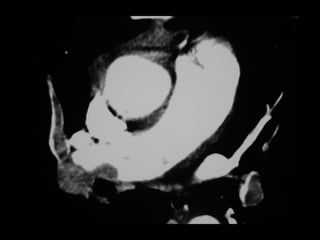

 Masculino, 70 anos

 Síncope após viagem de avião em classe

executiva (10h)

 AP:

 TEP há 12 anos em pós-operatório ortopédico

 Hiperplasia prostática benigna

▪ Início recente de doxazosina (alfa-bloqueador / vasodilatador)



EF: FC 92 bpm, SpO2 96% a.a.